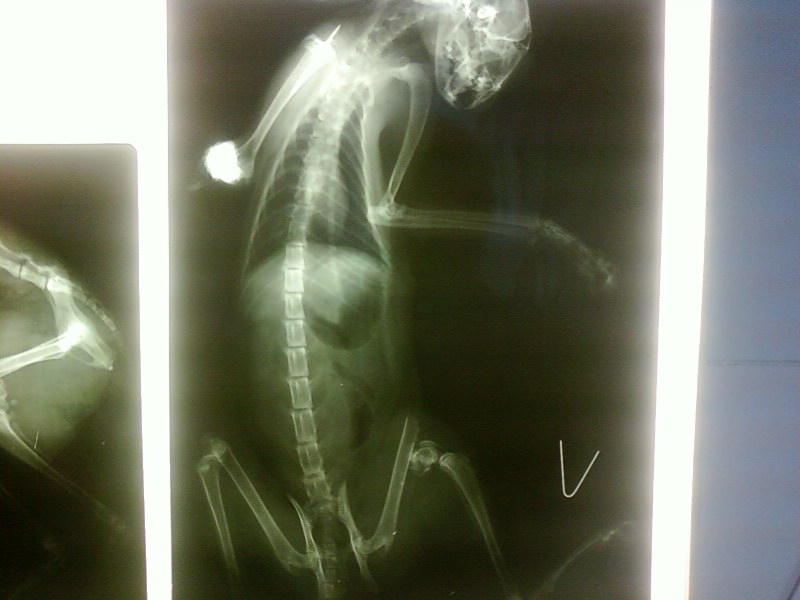

2 дня назад по великой случайности он выпал из окна с 8 этажа, в тот же час мы поехали в клинику, сперва в Энималз, но там мы так очереди не дождались и поехали на Фрунзе 57/1, забыл название. Там нам сделали снимки и сказали нужна операция. Посоветовавший по телефону с одни врачем, он сказал можно и не делать, попробовать в клинике сделать, ну что-то типо гипсовой накладки или как там, в общем я не понял. Пока он дома, лежит под уколами, отходит от шока, я бы хотел с вами посоветоваться, посмотрите пожалуйста фото, прокомментируйте. У него сотрясение и что-то с мочевым пузырем ( ушиб) , врачи так и не сказали. Вывих передней лапки, его на снимке видно и сломана задняя.